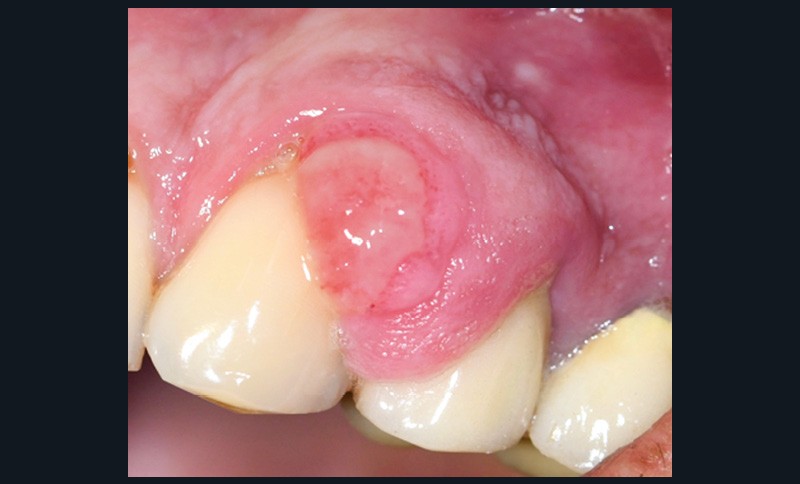

1. Épulis inflammatoire (plasmocytaire)

- Nodule indolore, pédiculé, érythémateux, parfois ulcéré (fig. 1a).

- Forme gravidique fréquente au 2e et 3e trimestres (fig. 1b). Favorisée par l’augmentation du taux de progestérone, œstrogènes, prostaglandines entraînant une vasodilatation.